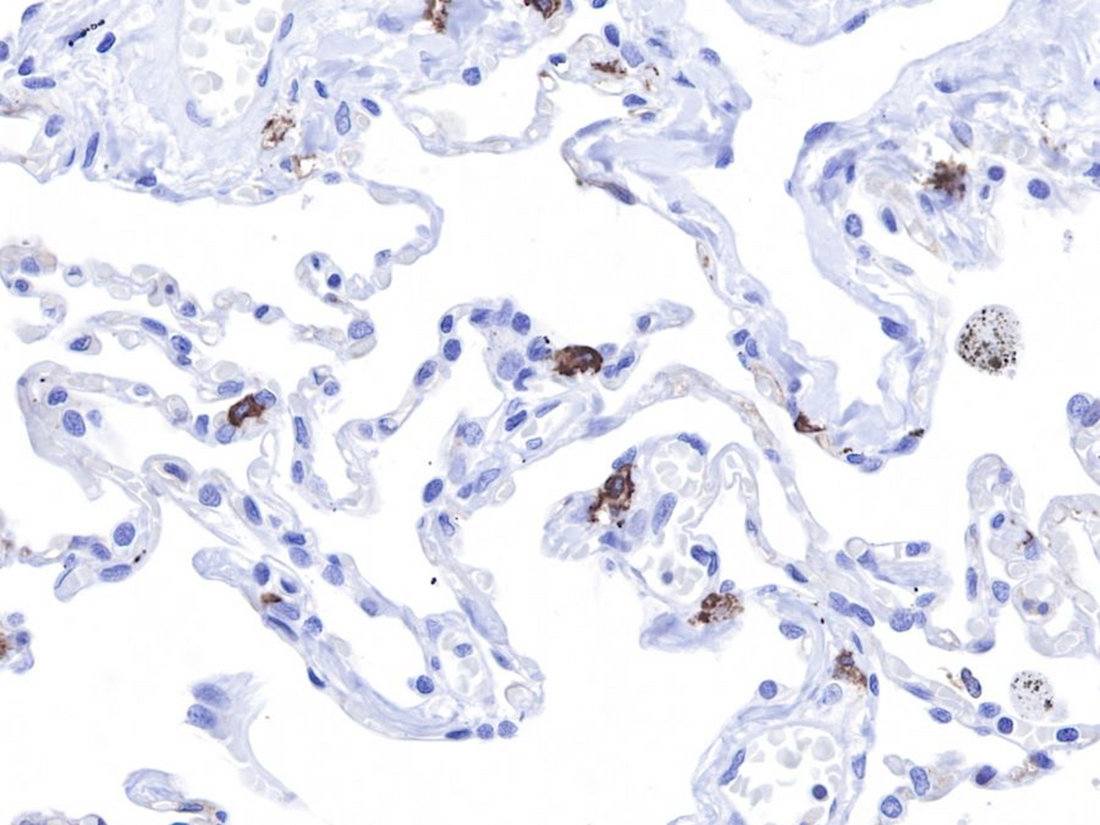

CD117 is a type III tyrosine kinase receptor encoded by the c-kit proto-oncogene. As a transmembrane protein for stem cell factor, it widely participates in the regulation of cell proliferation and differentiation. In normal tissues, it is expressed in mast cells, melanocytes, and gastrointestinal interstitial cells of Cajal, showing a co-localization staining pattern on cell membranes and cytoplasm. Additionally, some epithelial cells (such as breast, renal tubules, and thyroid follicular cells) may show weak cytoplasmic positive reactions.

Liquid cell control materials are a new type of immunohistochemical quality control material preserved in cell suspension form, with intact subcellular structures that can simulate the expression patterns of target proteins in real tissues. In CD117 detection, these control materials can exhibit the following typical staining characteristics:

- Positive control: 40%-60% of cells show moderate to strong complete membrane staining

- Negative control: All cells show no specific staining